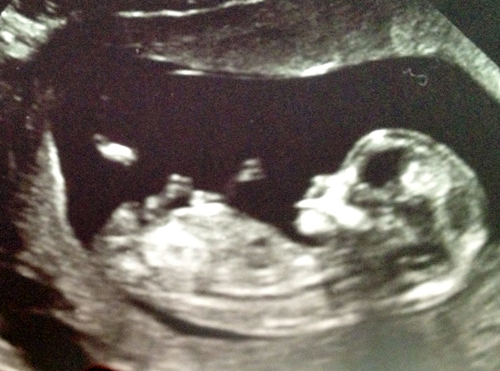

here is the pic from 12 weeks

Attachment 6837